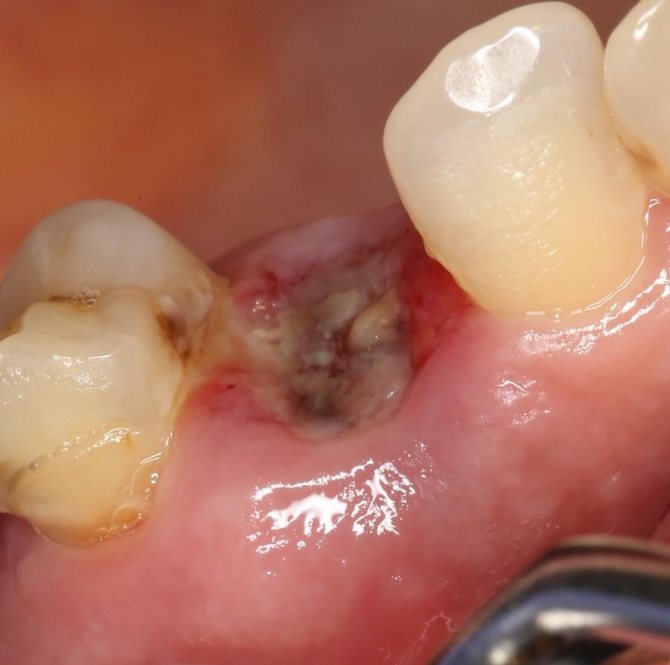

Хирургическое

Проводится при значительном разрастании опухоли посредством полного ее удаления. Операция подразумевает ее рассечение, и проходит в несколько этапов:

- Введение анестезии (в зависимости от клиники эпулиса, делается местное или общее обезболивание).

- Как только подействует анестетик, врач, отступив от ножки нароста 1-2 мм, надрезает вокруг него мягкие ткани десны на всю их глубину, захватывая надкостницу.

- Лоскут по всей окружности отслаивают.

- Если заболевание затронуло костную ткань, проводится препарирование пораженной области до здоровых тканей.

- Раневая поверхность прочищается, промывается антисептическим раствором и покрывается тампоном, пропитанным йодоформным составом.

- Если область поражения обширная, ее края стягиваются швами.

Расположенные рядом зубы вырываются только при их подвижности (при III степени) или при оголении их корней на 2/3 длины.